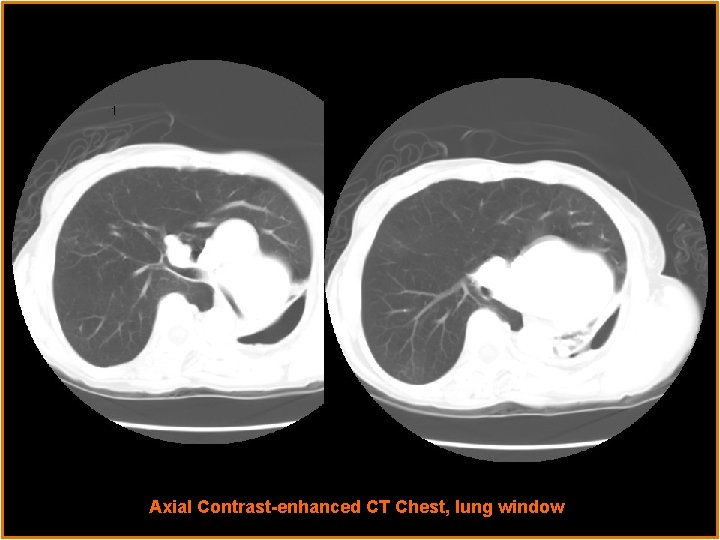

Radiological Presentations Axial Contrast-enhanced CT Chest, lung window

Findings Ipsilateral mediastinal and cardiac displacement Contralateral lung hyperinflation and herniation beyond the midline Bronchiectasis Hypoplastic lung with lack of Patent hypoplastic left main bronchus alveolar aeration Loculated pneumothorax

Findings Small and abruptly terminated left pulmonary artery Left superior pulmonary vein Elevation of left hemidiaphragm Contralateral lung hyperinflation and herniation beyond the midline